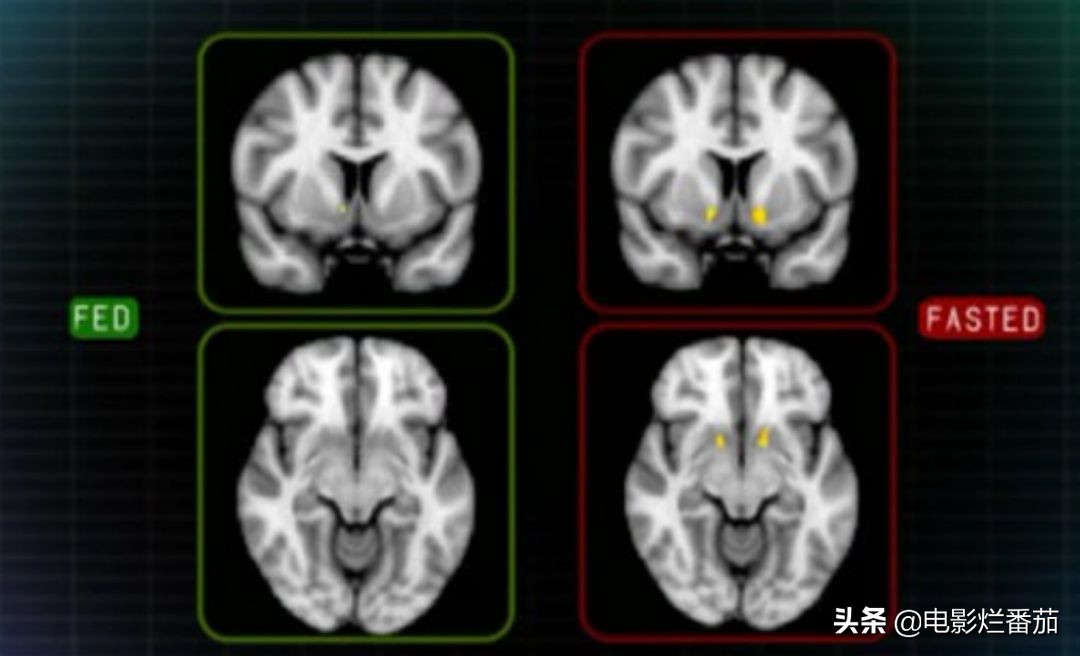

在《瘦身十律》中,科学家做了一个在饱腹与饥饿两种状态下,人在看到高热量食物与低卡食物时大脑做出的反映。

结果表明,在饱腹时,寡淡的蔬菜沙拉与甜美的蛋糕对人的吸引力是一致的,但是在饥饿时,大脑在眼睛看到高热量食物时会明显活跃,迫使你食用高热量食物来补充体能。

因此,如果你将三餐减掉一餐,往往意味着你在下一餐中会吃更多更容易发胖的食物,得不偿失。